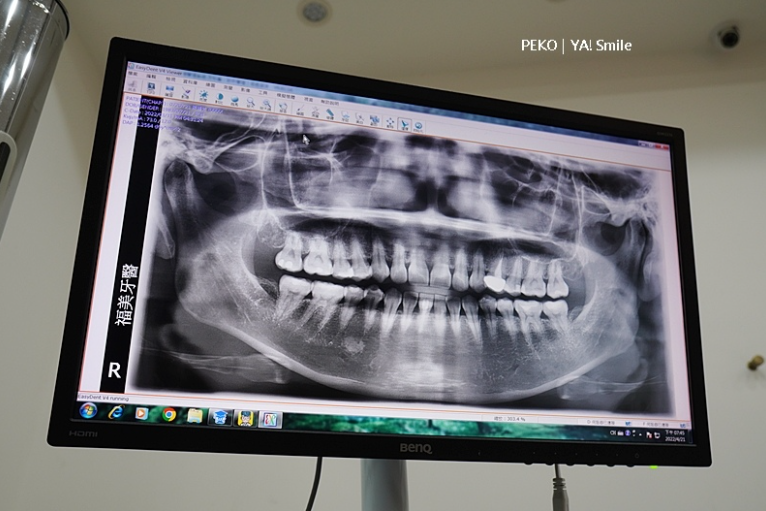

你知道自己的牙齒長怎樣嗎?

沒想到「ya!smile」竟然提供3D齒模,這個也太妙了,看了3D齒模會更清楚知道牙齒歪斜的程度,有特別標示的就是重點調整部位。